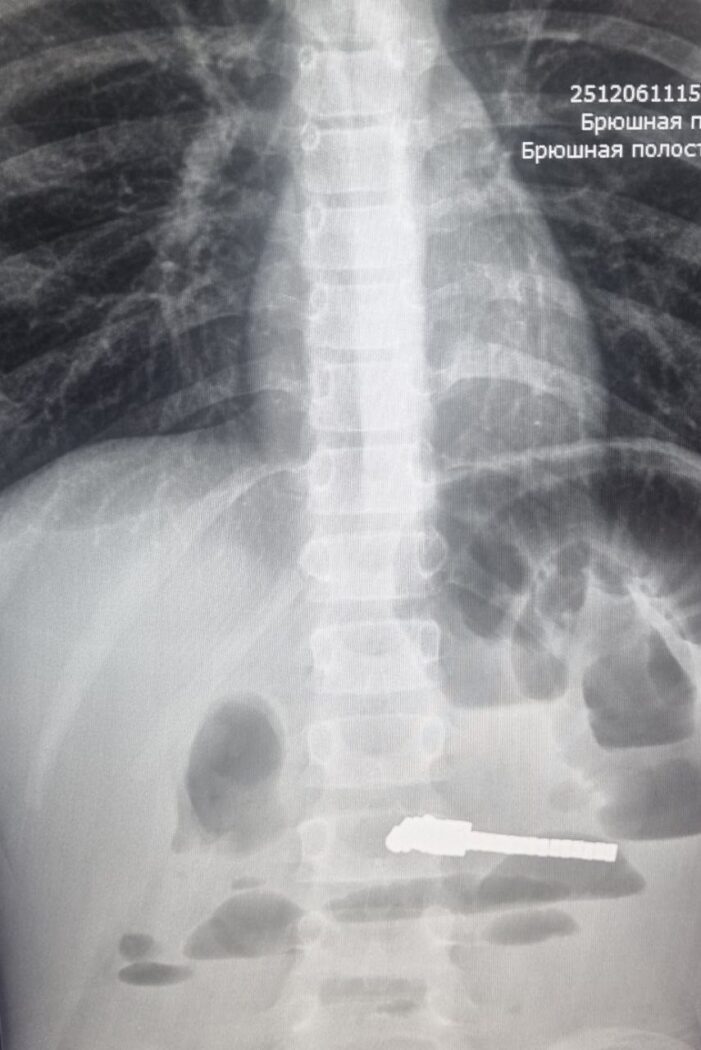

Как рассказала главный врач больницы Евгения Аверкина, маленький пациент поступил с жалобами на сильную боль в животе и рвоту. Доктора провели рентгенологическое исследование и обнаружили множество инородных тел в кишечнике, которые привели к его непроходимости.